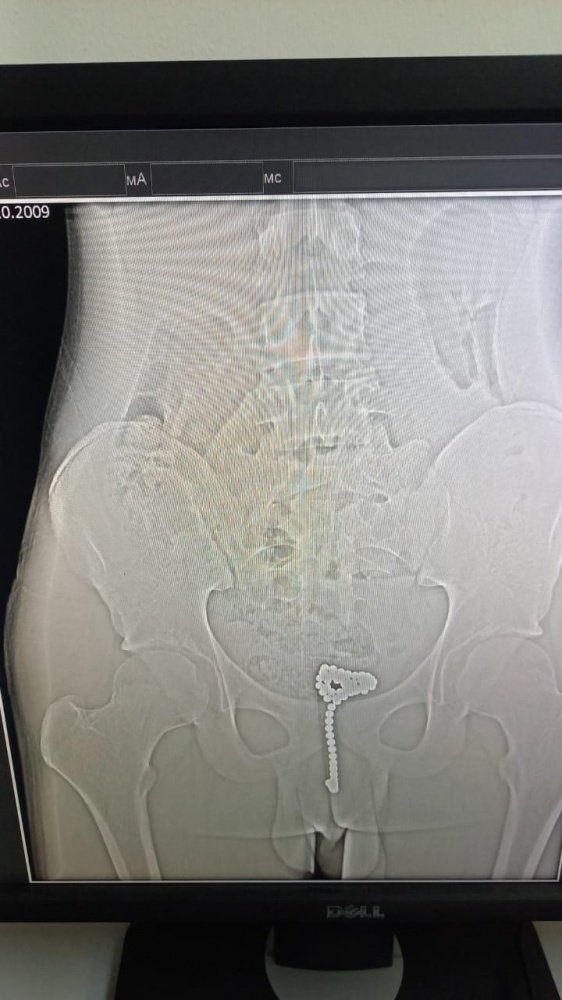

Хирурги городской больницы № 1 в Новороссийске столкнулись с необычной подростковой «шалостью». К ним доставили 14-летнего пациента, который поместил себе в уретру множество магнитных шариков. Разумеется, спустя время самочувствие мальчика ухудшилось, ему потребовалось срочное вмешательство.

Сначала подростку провели диагностическую уретроскопию с цистоскопией. Однако попытка извлечь шарики эндоскопически успехом не увенчалась и пришлось выполнять открытую операцию. Она прошла успешно.